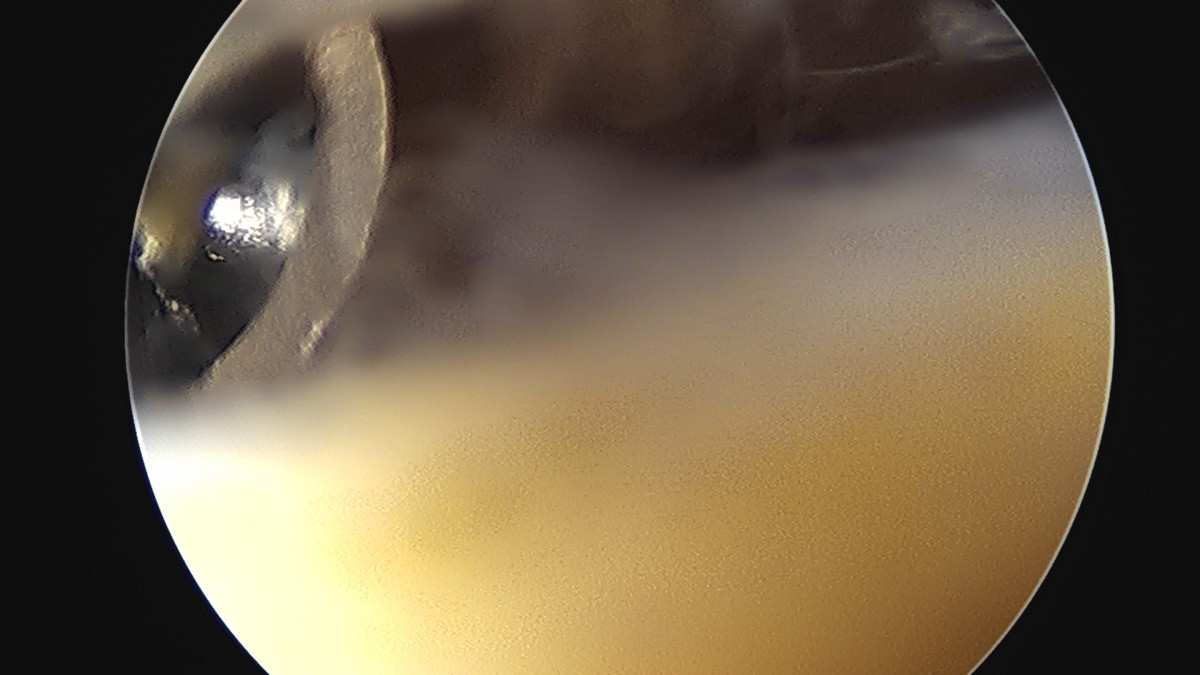

이재상원장님 어깨 견봉하 감압술 및 관절낭 이완술 류정O 환자

작성자 최고관리자 댓글 0건 조회 808회 작성일 25-09-16 15:30